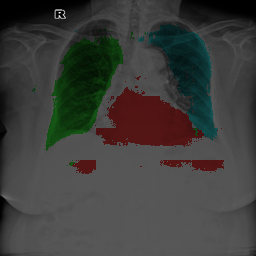

To bridge the methodological gaps when only small-scale partially labeled data is available, we propose a simple yet efficient framework Vicinal Labels Under Uncertainty (VLUU) by exploring the statistical similarity of human structures (e.g. shape, size, location) among different patients. See Fig. 1 for an illustration of such a similarity. The proposed framework is motivated by vicinal risk minimization (VRM) [11], where the fully labeled vicinal examples are generated by linearly combining randomly sampled partial labels with a weight randomly sampled from a Dirichlet distribution. These vicinal examples allow us to transform the partially supervised problem into a fully supervised one. That is to say, we can utilize any existing supervised segmentation networks and loss functions to solve partially supervised problems. The generated vicinal labels contain uncertainty regions where classes of interest could potentially overlap. We utilize these uncertainties in the training process to improve the robustness of DL models.

In standard adversarial training, the segmentation network and the discriminator play a zero-sum game. The discriminator is trained to discriminate the prediction masks produced by the segmentation network from the ground truth masks. Meanwhile, the segmentation network is trained to confuse the discriminator by producing realistic prediction masks. Adversarial training benefits from the human structure similarity as it makes the unknown true label distributions easier to be caught by the discriminator than for general objects [38]. In other words, there is smaller instance-wise variation in the size, shape, and location of human organs (or structures), as shown in Fig. 1, than for general objects.